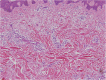

There has been a long-standing need for guidelines on the diagnosis and treatment of keloids and hypertrophic scars that are based on an understanding of the pathomechanisms that underlie these skin fibrotic diseases. This is particularly true for clinicians who deal with Asian and African patients because these ethnicities are highly prone to these diseases. By contrast, Caucasians are less likely to develop keloids and hypertrophic scars, and if they do, the scars tend not to be severe. This ethnic disparity also means that countries vary in terms of their differential diagnostic algorithms. The lack of clear treatment guidelines also means that primary care physicians are currently applying a hotchpotch of treatments, with uneven outcomes. To overcome these issues, the Japan Scar Workshop (JSW) has created a tool that allows clinicians to objectively diagnose and distinguish between keloids, hypertrophic scars, and mature scars. This tool is called the JSW Scar Scale (JSS) and it involves scoring the risk factors of the individual patients and the affected areas. The tool is simple and easy to use. As a result, even physicians who are not accustomed to keloids and hypertrophic scars can easily diagnose them and judge their severity. The JSW has also established a committee that, in cooperation with outside experts in various fields, has prepared a Consensus Document on keloid and hypertrophic scar treatment guidelines. These guidelines are simple and will allow even inexperienced clinicians to choose the most appropriate treatment strategy. The Consensus Document is provided in this article. It describes (1) the diagnostic algorithm for pathological scars and how to differentiate them from clinically similar benign and malignant tumors, (2) the general treatment algorithms for keloids and hypertrophic scars at different medical facilities, (3) the rationale behind each treatment for keloids and hypertrophic scars, and (4) the body site-specific treatment protocols for these scars. We believe that this Consensus Document will be helpful for physicians from all over the world who treat keloids and hypertrophic scars.